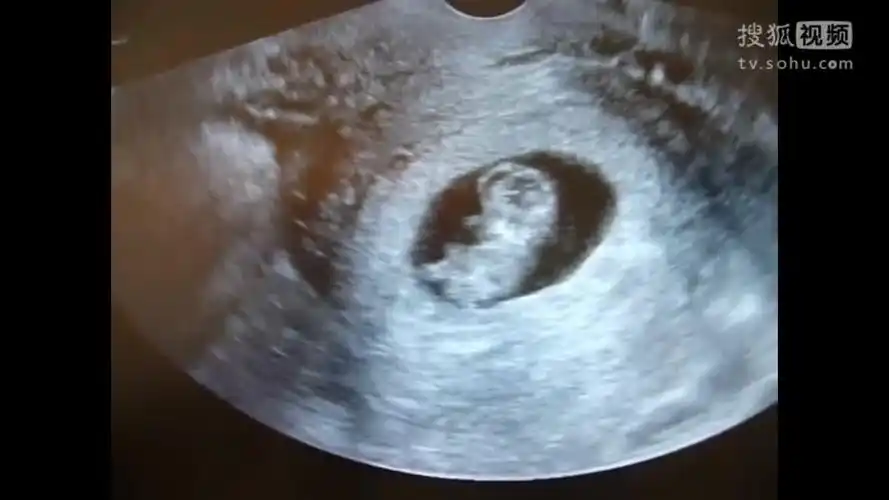

早期确定妊娠的 a href="#" data-lemmaid="687882">b超 /a>诊断依据

月经的第1天来计算,但是有些月经不太规律,甚至有些妈妈她是意外怀孕

怀孕10周去做b超,惊喜的发现宝宝在里面动,连医生都说很少见-母婴亲子